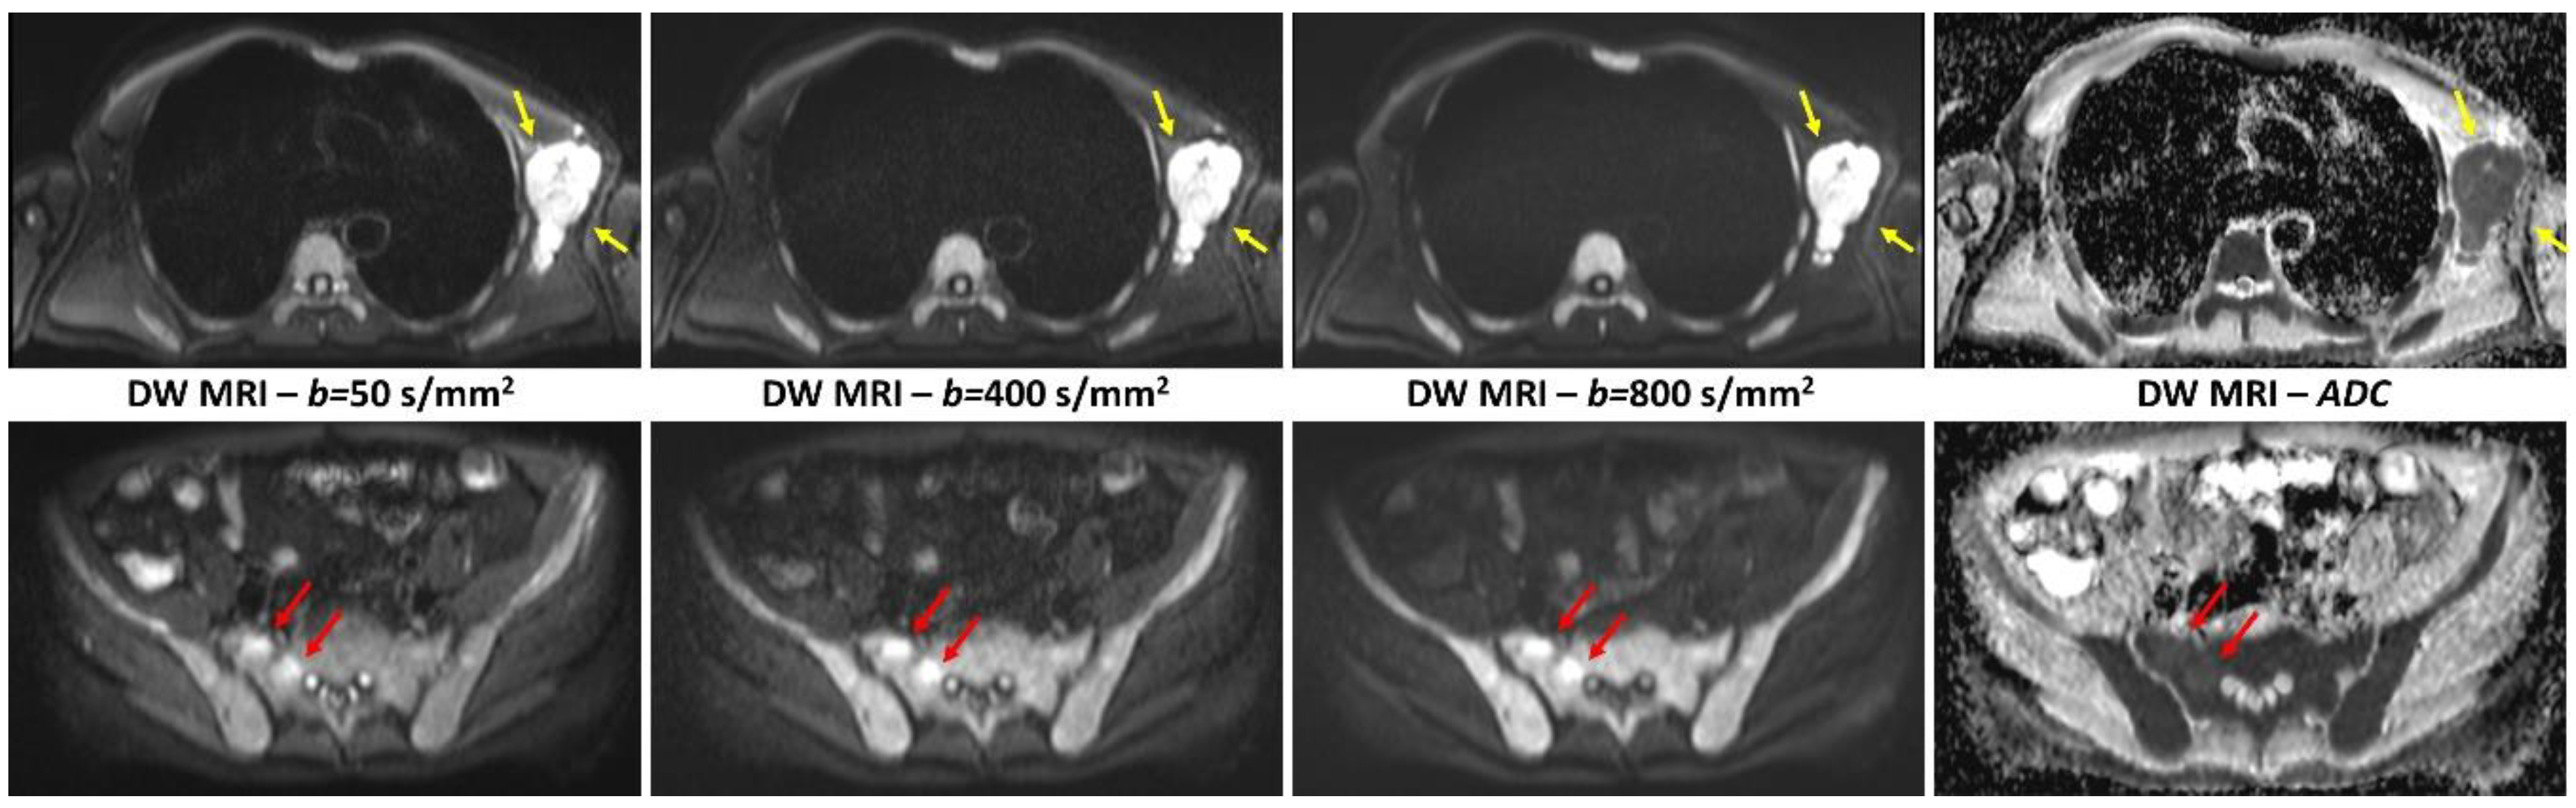

2.3. Whole-Body Diffusion-Weighted Imaging